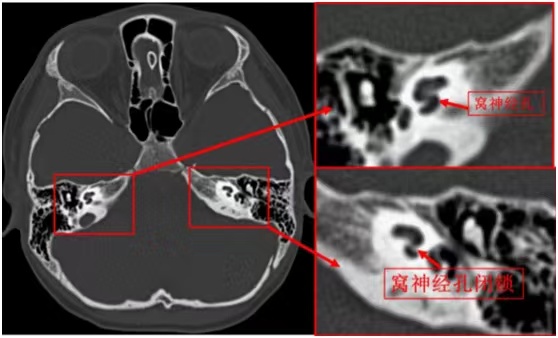

为了进一步确诊,于峰开具了中内耳 CT薄层、磁共振内耳和水成像检查(此检查可获得薄层、高空间分辨力的图像来显示内耳细微结构及穿行于内耳道之间的神经和血管)。

放射科副主任医师李艳梅通过询问患者病史,仔细查看扬扬的磁共振及CT影像,发现他左侧蜗神经孔闭锁,蜗神经缺如,结合扬扬的纯音听阈测试结果,经科室讨论后认为扬扬为左侧耳蜗神经缺如,左侧窝神经孔闭锁。随后,梁治平主任专门与耳鼻喉临床医生进行了图像解读讨论。于峰为患者家长做了详细解析并给出了治疗方案。

患者的影像检查